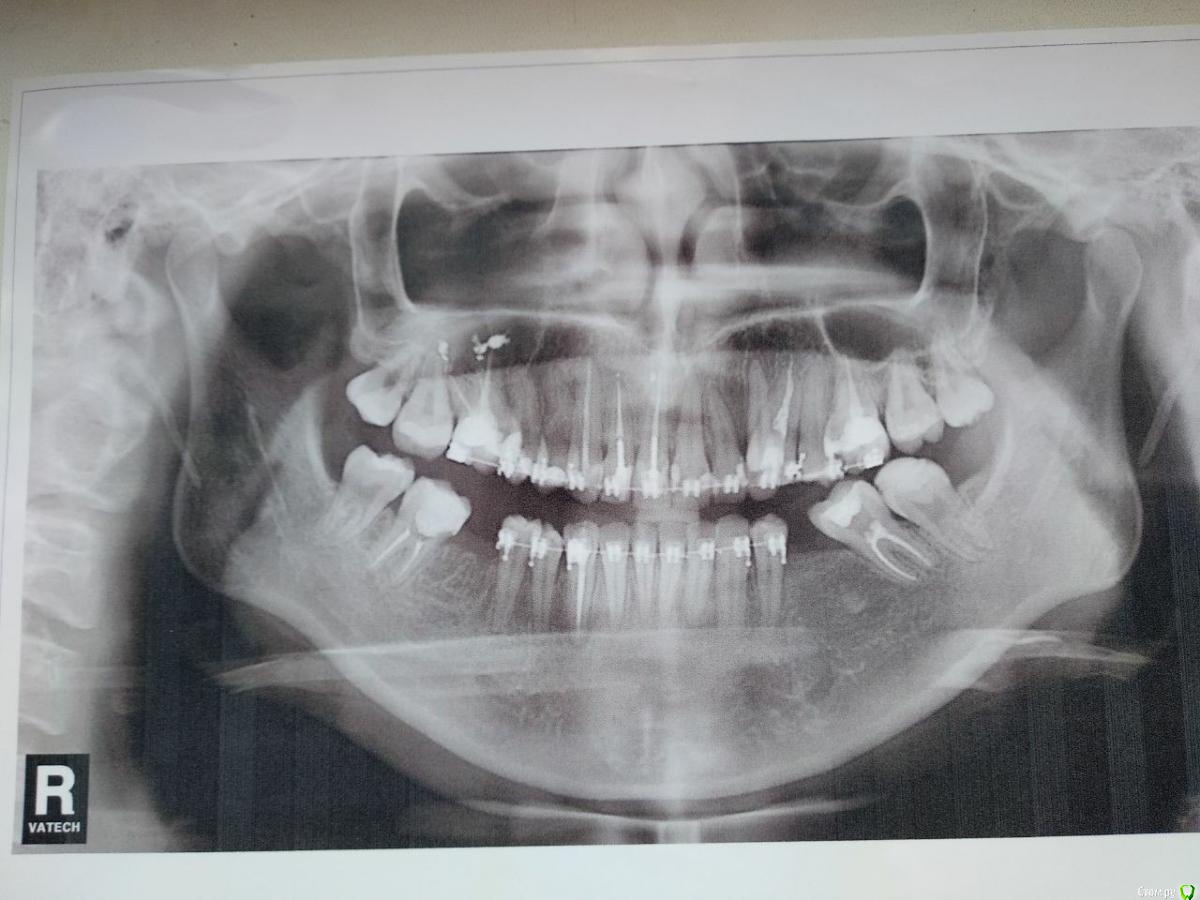

Добрый день. Носила брекеты 2года 3 месяца. Была небольшая скученность зубов (фото 1, начало лечения прилагается). Во время лечения брекетами очень сильно наклонились зубы вперед, еле закрывала рот. Удалили 8-ки с целью задвинуть их. Для этой цели ортодонт использовал маленькую пружинку которую ставил между зубами. В итоге-ничего не задвинулось,если не выдвинулось. Со временем, к снятию пришло ощущение, что нижняя челюсть не находит себе места, она висит, если зубы смыкать - то неудобно. Я тогда пошла сделала снимок рентген обоих суставов (фото 2 ). В заключении было сказано, что суставные щели внчс равномерны, суставные поверхности не изменены, при функциональных нагрузках визуализируется подвывих левого внчс. Я понесла это заключение ортодонту, он сказал что у меня все прекрасно, что этот подвывих есть у многих, и что он у меня скорее-всего был раньше. Я немного успокоилась. Но все таки ортодонта мучала мольбой чтоб исправил наклон передних зубов , но он уверял, что все хорошо, и что если сделать наклон, то корни передних зубов выйдут из десны и зубы будут держаться в слизистых... Это меня испугало. Центр нижней челюсти он не стал трогать, сказал, что это незаметно. И кстати нижние фронтальные зубы тоже  имеют наклон вперед. Из за этого при смыкании у меня нижние передние зубы упираются в верхние зубы под углом. Из-за этого чувствую при смыкании как передние зубы шатаются выдвигаясь еще больше наружу. Все таки меня уговорили снять брекеты, я надеялась, что после снятия мне будет легче и все устаканится. Я планировала беременность, поэтому больше не могла столько заниматься зубами (к слову, последний год, в связи с переездом мне пришлось ездить к ортодонту 12 часов на поезде в одну сторону, тратить 5000 пару раз в месяц на дорогу). Снятие было в ноябре, прошло 4 месяца. Меня стали мучать жуткие головные боли, шею тянет, позвоночнику некомфортно, в области обоих висков при открывании рта очень сильно выпирает и заметна подвижность какой-то шишечки, наверное это суставная головка. есть ощущение, что нижняя челюсть сильно задвинута назад, либо это верхняя слишком выдвинута, прикус у меня был нормальный, а теперь, кажется дистальный. Наклон передних зубов такой сильный, что помещается палец когда зубы сжаты. Лицо стало очень худым и изможденным, мне 26 лет, щеки впали сильно. Мышцы лица в области висков и щек очень сильно напряжены, постоянно какие то очень сильные похрустывания,Теперь начал болеть затылок,он начал хрустеть. жить стало просто невозможно. Какое-то состояние апатии, снижена концентрация внимании. Я не знаю к кому обратиться и что мне с этим делать.  Помогите, пожалуйста, как поступить